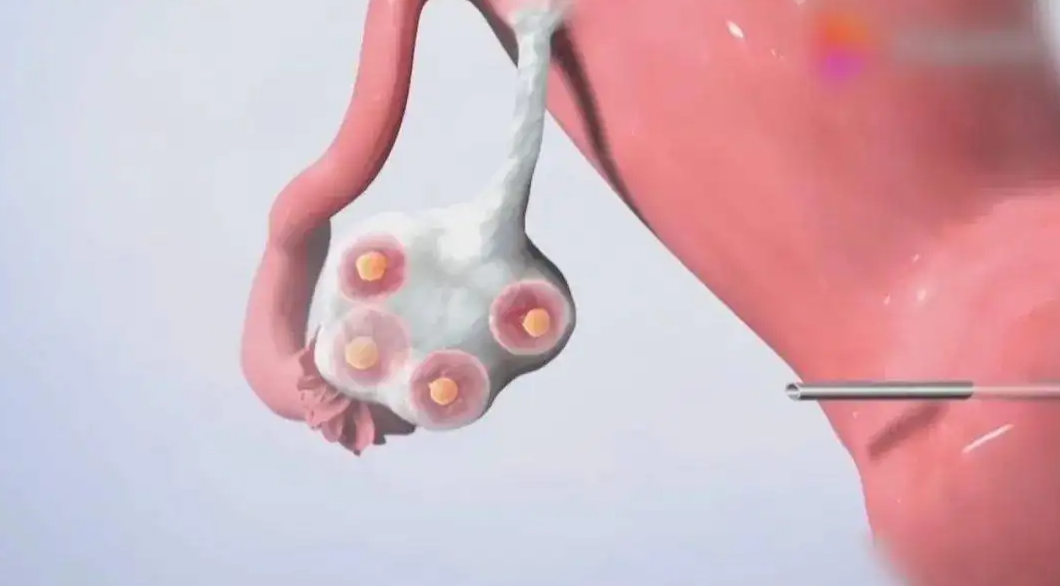

取卵是医生在B超监测下,用一根细穿刺针经阴道直达卵巢吸取卵泡液,之后通过显徼镜找寻卵子。一旦卵泡张力比较差,取卵就可能比较困难,抽吸时卵泡壁塌陷太早,也不太容易吸净内容物,从而使卵子遗漏。另外,若女性卵泡里的卵子不能从卵泡壁上脱落下来,也会导致取不到卵子。

取卵时机是决定获卵率的关键。如果时间把握不到位,会出现因卵泡发育不成熟而取不到卵子,或卵子过于成熟、老化流失的现象,从而降低获卵数量。所以用药第7天,专家会查看女性雌激素、孕酮和卵泡的数值,把握合适的取卵时机。当有1~2个卵泡发育直径≥18mm或2~3个≥17mm时,就开始注射破卵针,待36小时后进行取卵。

取卵时,专业的麻醉师会根据女性的身高、体重等指标进行合理的麻醉用药,在女性进入睡眠状态后,HRC专家会在B超的引导下进行探针穿刺,将含有卵子的液体抽出来,之后在显微镜下取出卵子。